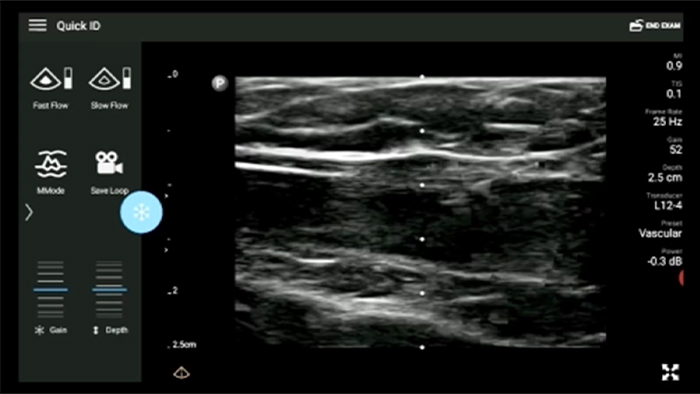

See for yourself Get the full picture with clear whole-body imagery for a fast, accurate response during an emergency.

Lumify transducers for emergency medicine

Lumify L12-4 broadband linear array transducer

• 4 to 1 MHz extended operating frequency range • 2D, color Doppler, M-mode, advanced XRES and multivariate harmonic imaging • High-resolution imaging for abdominal and cardiac applications: Cardiac, OB/GYN, Lung, Abdomen and FAST imaging preset optimizations Lumify aids life-saving technology in prehospital setting